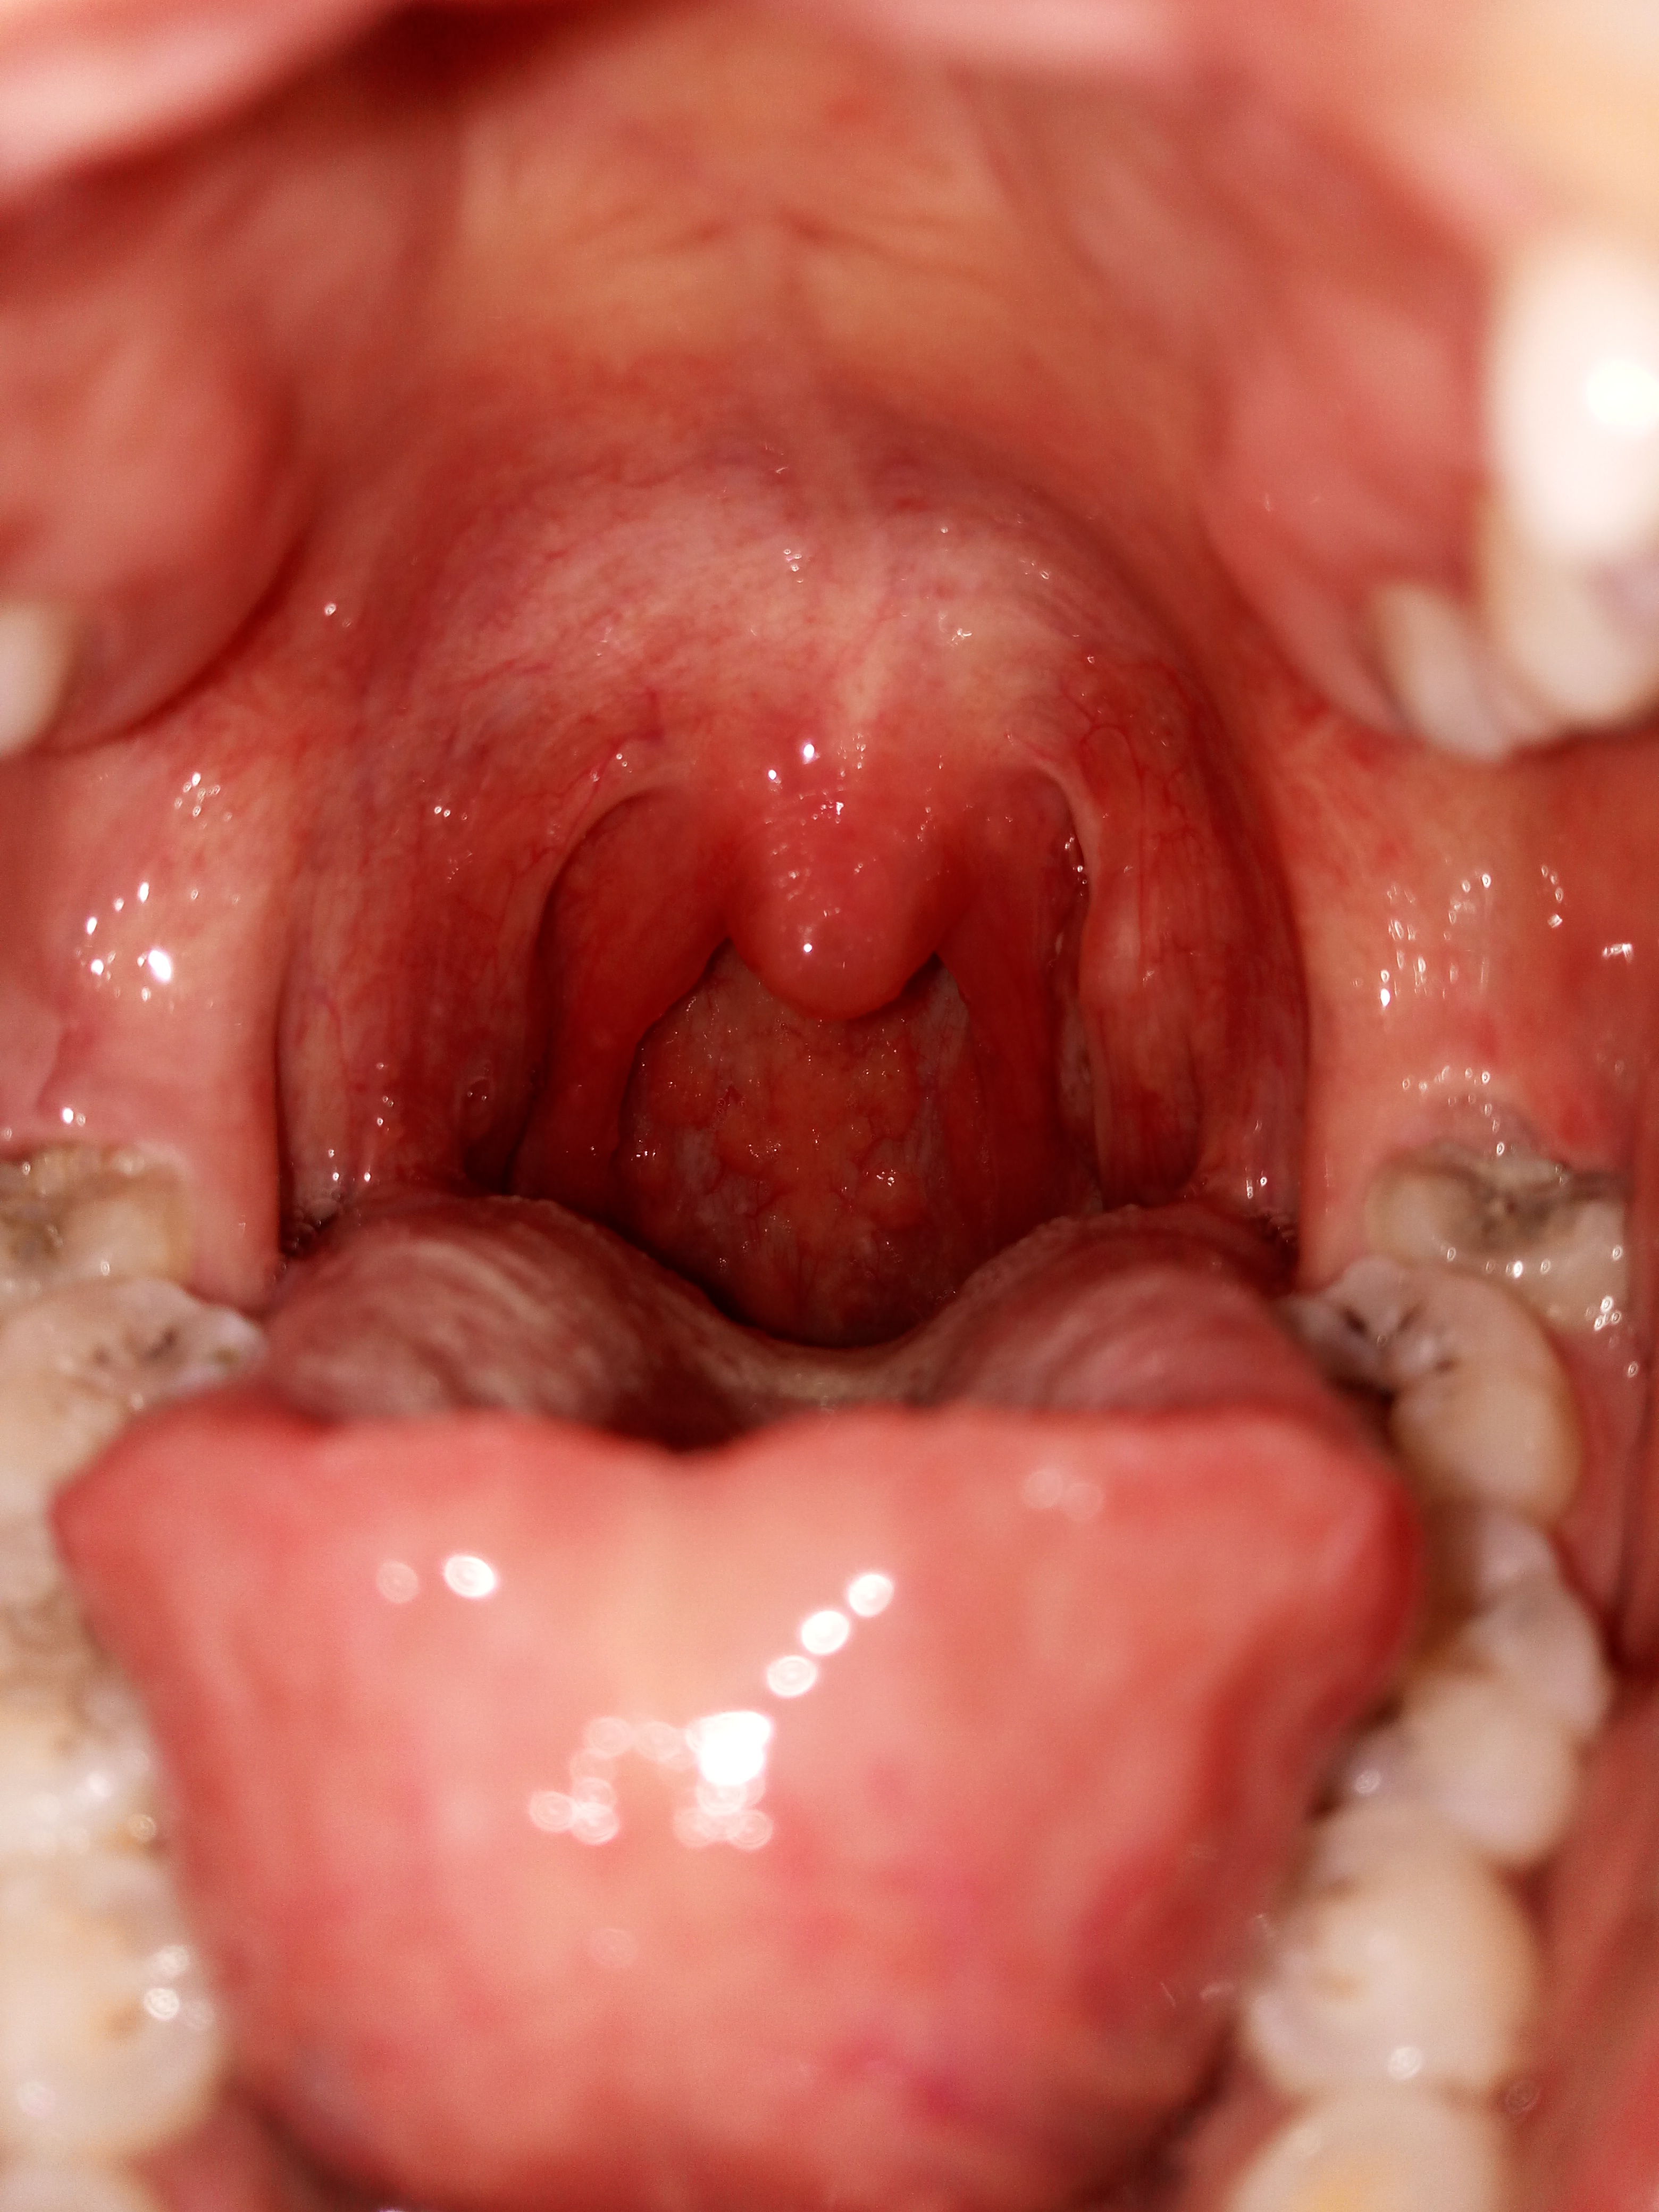

一直有异物感,看了下镜子吓到了,小舌头肿起来了,后面好像都发炎了,不

吃快卖榨菜肉丝,吃一半突然感觉口腔很痛,照片拍下来发现小舌头一边

喝水,咽口水都疼是怎么回事,白色哪里像泡一样的是什么,小舌头周围

吐口水都痛,我现在状况是不是很严重啊. 有照片速度来看看